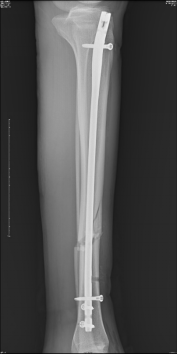

術(shù)后影像資料